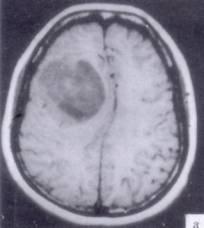

病历摘要:??患者男性,52岁。头痛伴呕吐2月,呕吐呈喷射性。既往身体健康。体检:神清,表情淡漠,反应迟钝,双眼底视神经乳头明显水肿,左鼻唇沟稍浅,左腹壁...

问题 病历摘要:??患者男性,52岁。头痛伴呕吐2月,呕吐呈喷射性。既往身体健康。体检:神清,表情淡漠,反应迟钝,双眼底视神经乳头明显水肿,左鼻唇沟稍浅,左腹壁反射减弱,左上下肢肌力4级,左Babinski征(-)。 下列关于脑叶切除术范围的叙述哪些是正确的?